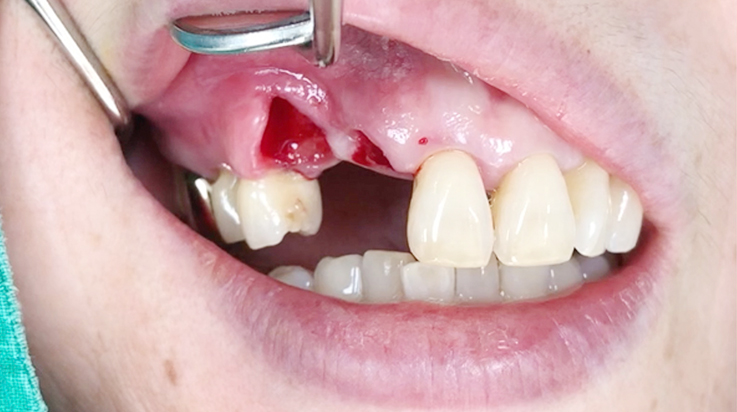

Horizontal ridge augmentation

A surgical procedure to increase the width of alveolar ridge which have been resorbed after tooth or teeth were lost

A surgical procedure using resorbable membrane